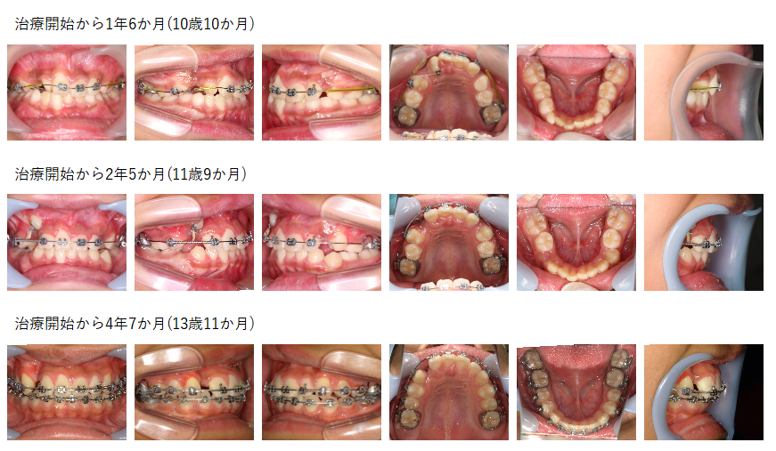

【治療例 K5102】初診時年齢:8歳2か月 / 性別:女性 / 主訴:上の前歯が出ている

治療の概要:下顎骨が後退した著しい上顎前突症例でした。第1期治療では、下顎骨の前方誘導は図るために上顎に咬合斜面板を装着しました。その後、上顎に2×4装置とヘッドギアで上顎骨の成長抑制を図りました。第2期治療では残りの永久歯にマルチブラケット装置を装着しました。その結果、綺麗な側貌と緊密な咬合を獲得できました。

主訴: 上の前歯が出ている

診断名: 上顎中切歯の著しい唇側傾斜を伴う上顎前突

使用した主な装置: サービカルヘッドギア、咬合挙上板、マルチブラケット装置、顎間ゴム

抜歯/非抜歯および抜歯部位: 非抜歯(ただし、乳歯の抜歯はあり)

治療期間:4年7か月

治療回数:66回